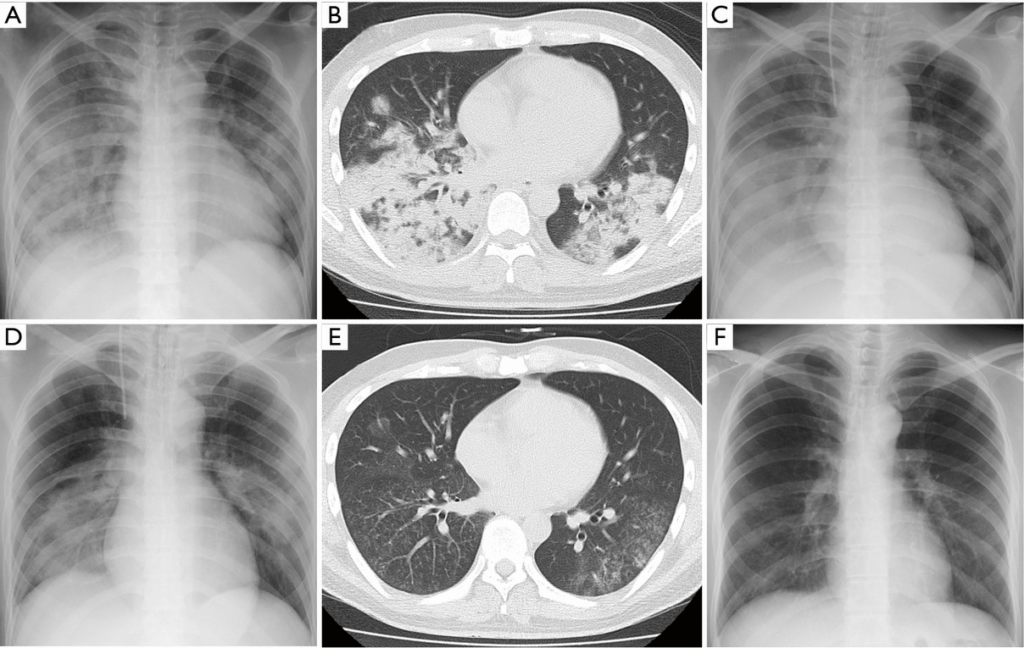

При рентгенологическом исследовании легких обычно выявляют очагово-инфильтративные изменения и плевральный выпот. КТ органов грудной клетки может быть целесообразной альтернативой рентгенографии в ряде ситуаций:

- При наличии очевидной клинической симптоматики пневомнии и отсутствии изменений на рентгенограмме

- В случаях, когда при обследовании больного с предполагаемой пневмонией выявлены нетипичные изменения (обтурационный ателектаз, инфаркт легкого при ТЭЛА, абсцесс легкого и пр.)

- Рецидивирующая пневмония, при которой инфильтративные изменения возникают в одной и той же доле (сегменте), или затяжная пневмония, при которой длительность существования инфильтративных изменений в легочной ткани превышает 4 недели